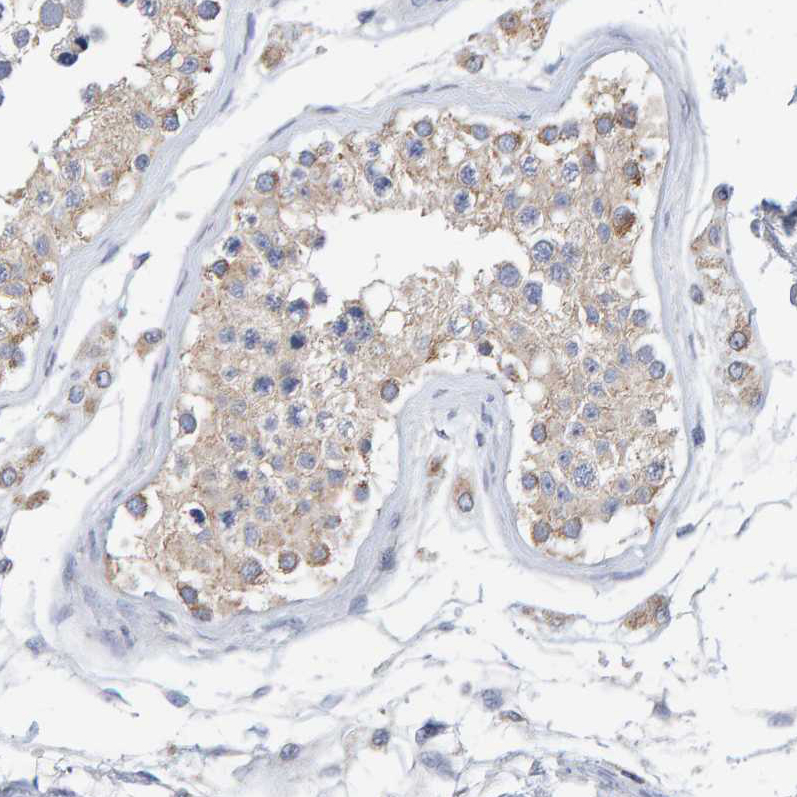

Immunohistochemical staining of human colon, kidney, liver and testis using Anti-SGPL1 antibody HPA021125 (A) shows similar protein distribution across tissues to independent antibody HPA023086 (B).